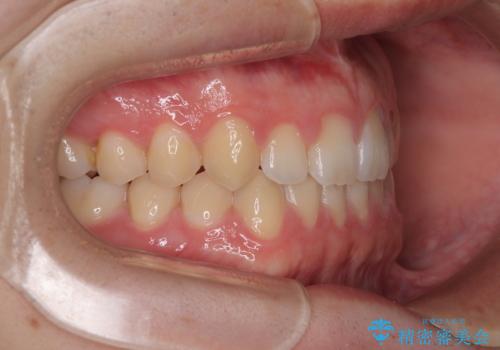

- インビザラインモデレート

- 11ヶ月

- 5-10回

そこで矯正治療と並行して**MFT(口腔筋機能療法)**を実施し、舌や口周囲筋の正しい使い方を習得していただきました。

マウスピース矯正特有の奥歯への圧下により、一時的に噛みにくさを感じる場面もありましたが、

装着時間の調整と経過観察を行うことで症状は改善し、スムーズに治療を完了しました。